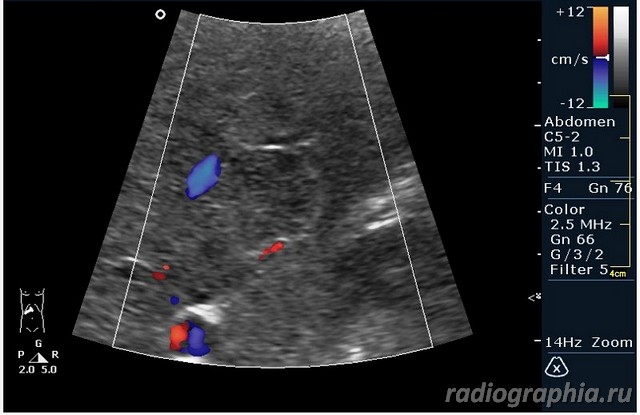

УЗИ печени. Женщина 37 лет. Жалобы на боли в эпигастрии; в печени обнаружено такое образование...

Считаю,что это опухоль,имеет неоднородную структуру,четкий контур,прорастает в сосуд(есть один такой скан) И,вообще,вся поверхность печени НЕСПОКОЙНАЯ,могут быть мелкие МТ.Интересно,что на КТ?

так и хочется назвать это метастазами но уж очень они красивые и доброжелательние по структуре (изоехогенные по отношению к структуре печени) и они больше компресирують чем проростают, склонен к ответу о доброкачественной гиперплазии. так что же на КТ?

гемангиома,рядом питающий сосуд

Мне тоже нравится версия, что это - гемангиома.Нелли писал(а):гемангиома,рядом питающий сосуд